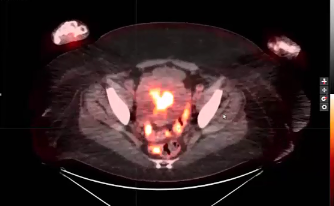

endometrial adenocarcinoma, para-aortic nodes, PET CT, diabetes, charcot arthropathy, groin nodes, pelvis, negative cervical margins, cisplatin, small bowel, Harkenrider, contouring, MRI, tumor, vaginal bleeding, relapse, persistence, cylinder, dose distribution, dosimetry, brachytherapy, fractio...

squamous cell carcinoma, dysplasia, PET, SIB, brachytherapy, endocervical, MRI, nodal location, inguinofemoral, right external iliac, CTV, deescalation, dosimetry, sigmoid, hysterectomy, concurrent chemoradiation, stenotic cervix, abdominal infection, external planning, avoid structure, antibioti...